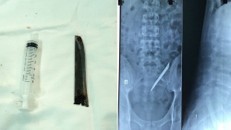

ưỡi dao Thái Lan trong cơ thể bệnh nhân trên phim X-quang và lưỡi dao khi được lấy ra.

Lưỡi dao dài 12cm 'sống' trong cơ thể nam thanh niên suốt 4 năm

(Ngày Nay) - Lưỡi dao dài khoảng 12 cm đã được các sĩ BV Nhân dân 115 TP.HCM lấy ra khỏi người nam thanh niên 24 tuổi.